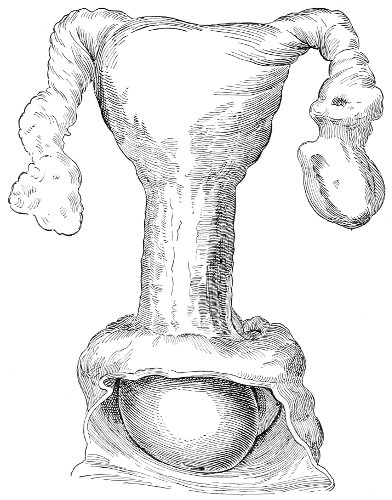

An accurate knowledge of the anatomy and mechanism of the female perineum is essential to an understanding of the nature and treatment of injuries to this structure. The anatomical structures lying between the anus behind and the symphysis pubis in front are those that most directly interest the gynecologist. Proceeding from 57 below upward, we find the following structures lying in superimposed planes: the skin, the superficial fascia, the deep layer of the superficial fascia, the transversus perinæi and the sphincter vaginæ muscles, the anterior layer of the triangular ligament, the posterior layer of the triangular ligament, the levator ani muscle (Fig. 19).

The vagina passes through these structures. They surround and support the ostium vaginæ as the fascia and muscles surround and support the opening of the rectum or the anus. The muscles and fasciæ are attached in the median line between the anus and the vagina, and therefore this part of the body, which is called the perineum, is supported or maintained in its 58 proper position by these various structures. The transversus perinæi arises from the ramus of the ischium and is inserted in the perineum. The bulbo-cavernosus, or sphincter vaginæ, arises in the perineum and is inserted in and about the clitoris. The inner fibers of the levator ani arise from the symphysis pubis and are inserted in the perineum and the lower part of the vagina (Fig. 20). When these muscles contract, their action, therefore, is to draw the perineum upward and forward. At the same time the anus is drawn upward and forward, and so also is the posterior margin of the ostium vaginæ and the lower portion of the posterior vaginal wall.

Fig. 20.—Dissection of female perineum, showing the deeper structures after removal of the levator and sphincter ani muscles.

The vagina has no circular sphincter like the anus, but 59 the vaginal month is kept closed by the action of the transversus perinæi, sphincter vaginæ, and levator ani muscles, which draw the perineum forward, and thus keep the posterior vaginal wall in apposition with the anterior wall.

Fig. 21.—Muscular floor of the pelvis seen from above.

This sling of muscles and fascia, which surrounds and supports the opening of the vagina, may readily be felt in the nulliparous woman by introducing the finger in the vagina and pressing backward and outward toward the ischio-rectal fossa. We then feel plainly, immediately within the ostium vaginæ, a firm resisting band of tissue, apparently about half an inch broad, embracing the posterior portion of the lower vagina. This band is formed by the inner edges of the various muscles and planes of fascia that have been described.